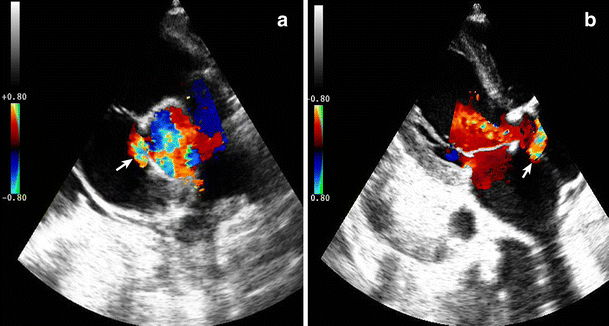

Transthoracic echocardiography was performed and showed a slightly dilated right ventricle in the presence of a ruptured SVA left-to-right shunt from the aorta into the right atrium in association with a bicuspid aortic valve (Fig. 1). We had planned surgery but the patient refused the operation. SVA is an uncommon condition and association with bicuspid aortic valve has been reported previously [1, 2]. Transoesophageal echocardiography and magnetic resonance imaging are useful for diagnosis and may help to delineate the anatomy further. Unfortunately, the patient did not give permission for further evaluation and treatment.

Fig. 1

Parasternal short- (a) and long-axis (b) view showing a ruptured sinus of Valsalva (arrow) with a bicuspid aortic valve